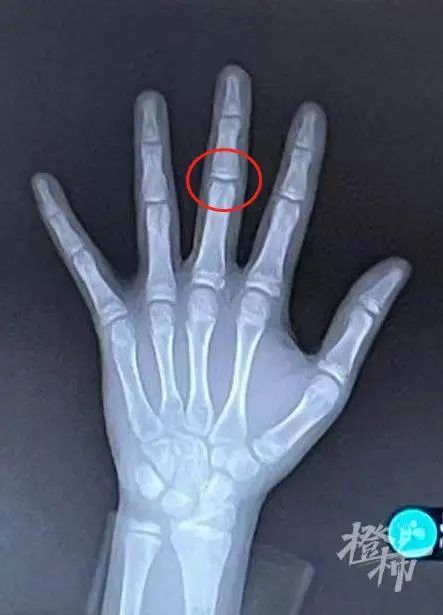

骨龄未闭合

骨龄已近闭合

GP图谱用起来比较简便,它将被评价的X片与发育程度相近的图谱标准片做整片比较,直到选择出发育程度最为相似的标准片,该标准片的骨龄即为被评价儿童的骨龄;

TW3计分法是给手部X片上的20块骨头打分,根据查分表格来断定儿童的骨龄,相对比较复杂。

GP法相对来说主观性较强、偏差大,这对医生的经验要求比较高。TW3法借助计算机辅助进行骨龄评估,更精细、更准确,但也更繁琐些。其实,不同的方法各有优缺点,对不同的年龄也有不同,比如GP法计算对小年龄骨龄会偏小,而TW3法对大年龄组略偏小。